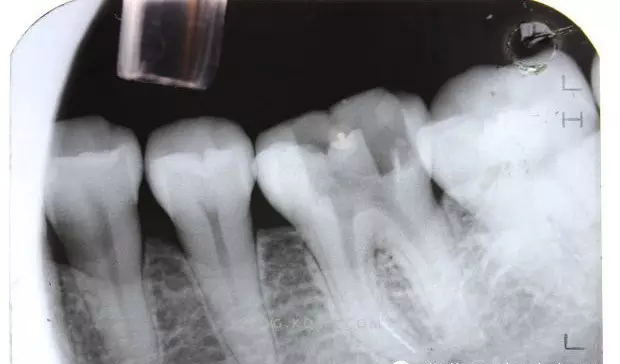

(1)通路建立:臨床操作中,X線(xiàn)明確斷針位置后,在根管顯微鏡(放大10~20倍)觀(guān)察下,先用帶柄根管銼插入根管,直到斷針冠方斷面,用止動(dòng)片標記,確定斷針深度。然后用K銼或者H銼將斷針上部的根管預備到30~40#,將GG鉆2#和3#尖 端磨平,使GG鉆尖 端平面的直徑大于斷針的直徑,用2?;蛘?#調磨后的GG鉆從根管口預備到斷針的位置,建立通道,使斷針以上部分根管明顯通暢,便于顯微鏡觀(guān)察和術(shù)中操作。